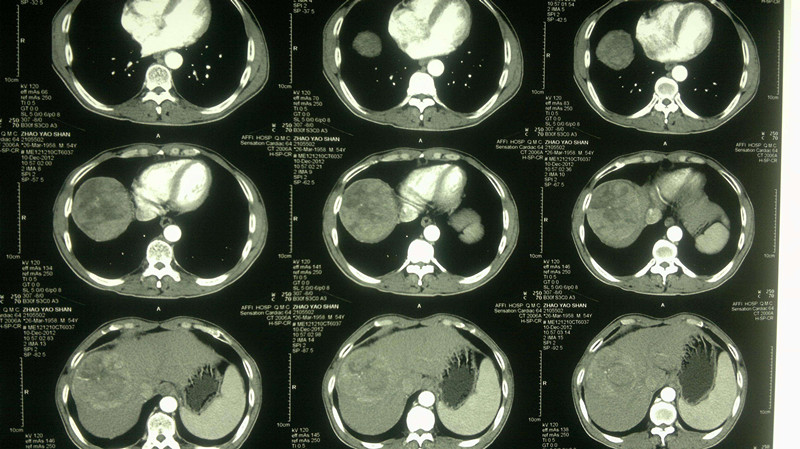

3. 肝腹水

正常人腹腔内有少量的游离腹水,一般为50毫升左右,起着维持脏器间润滑作用,当腹腔内出现过多游离液体时,称为腹水。(但是,这个病症比较少见,最常见的是肝硬化)。

6. 腹腔积液

正常状态下,人体腹腔内有少量液体(一般少于200ml),对肠道蠕动起润滑作用,超过200ml时,称为腹腔积液。比较常见的有心血管病、肝脏病、腹膜病、肾脏病、营养障碍病、恶性肿瘤腹腔转移、卵巢肿瘤、结缔策划疾病等,都有可能诱发腹腔积液。